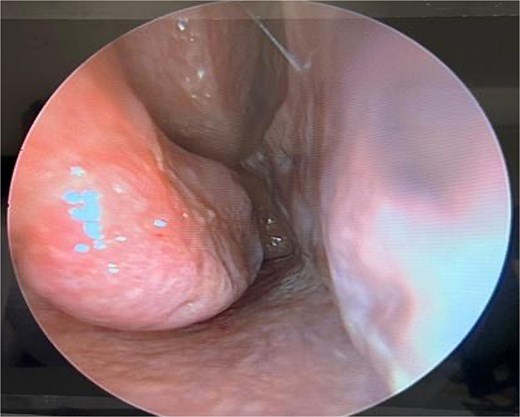

The surgical approach begins with endoscopic visualization of the deviated segment (Fig. 2).

Intraoperative endoscopic view of the deviated nasal septum prior to correction.